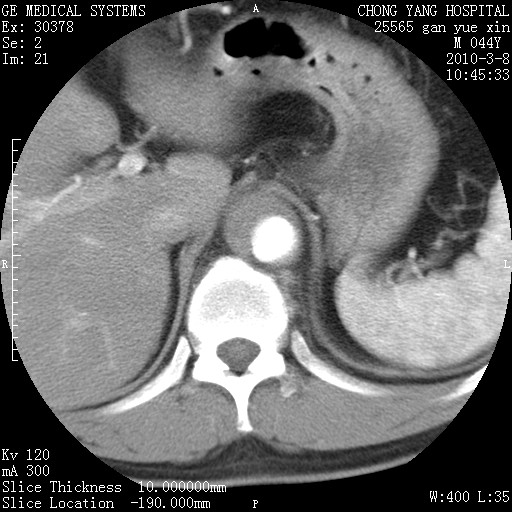

标题: CT24940:主动脉增强,典型病例。 [打印本页]

标题: CT24940:主动脉增强,典型病例。

夹层动脉瘤。

动脉夹层

夹层动脉瘤,典型

主动脉夹层。

动脉夹层的分型:

⒈debakey分型:根据主动脉夹层累及部位,分为三型:ⅰ型:原发破口位于升主动脉或主动脉弓部,夹层累及升主动脉、主动脉弓部、胸主动脉、腹主动脉大部或全部,少数可累及髂动脉。ⅱ型:原发破口位于升主动脉,夹层累及升主动脉,少数可累及部分主动脉弓。ⅲ型:原发破口位于左锁骨下动脉开口远端,根据夹层累及范围又分为ⅲa,ⅲb。ⅲa型:夹层累及胸主动脉。ⅲb型:夹层累及升主动脉、腹主动脉大部或全部。少数可累及髂动脉。

⒉stanford分型:a型:夹层累及升主动脉,无论远端范围如何。b型:夹层累及左锁骨下动脉开口以远的降主动脉。

夹层动脉瘤,少量胸水

夹层动脉瘤;左侧少量胸腔积液。

典型主动脉夹层。